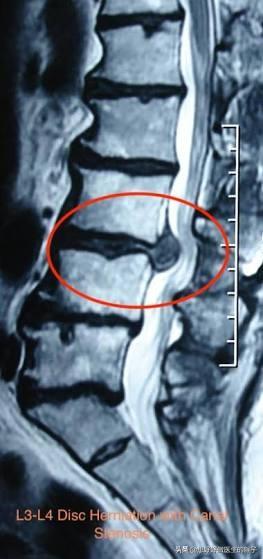

而将纤维传递到膝盖的神经位于腰部第二、第三和第四腰椎水平处。如果像椎间盘突出或关节炎导致的骨质增生压在这些部位的神经上,那么膝盖部位可能会感到疼痛,当突出位于腰二椎体的时候,患者就会表现为臀部的疼痛,然而一般这种情况是比较少见的,因为一般的腰椎间盘突出多数都位于腰4-5和腰5-骶1这两个节段。

●当间盘突出出现椎管狭窄的时候,患者除以上症状外还会表现出站立行走使症状加重,坐着几乎立即缓解的特点